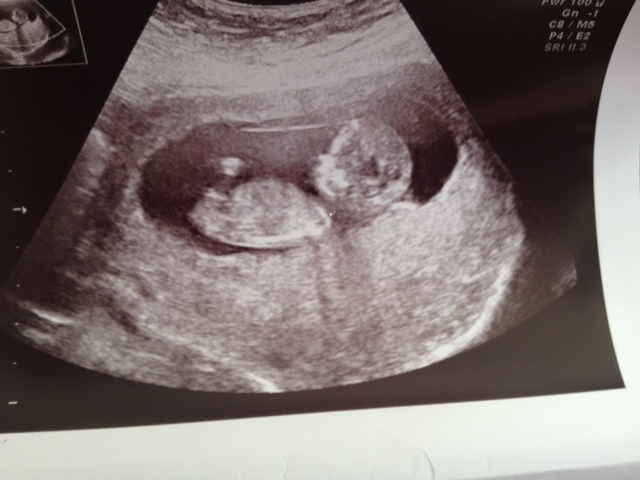

These are our 3 shots from our 12 week 4 day scan any predictions on Nub or Skull Theory Please?

boy first two pics showing boy nub

Pretty sure a sweet baby boy is in there :)

I think boy

I would guess boy. Congrats!

I am thinking boy :)

boy x